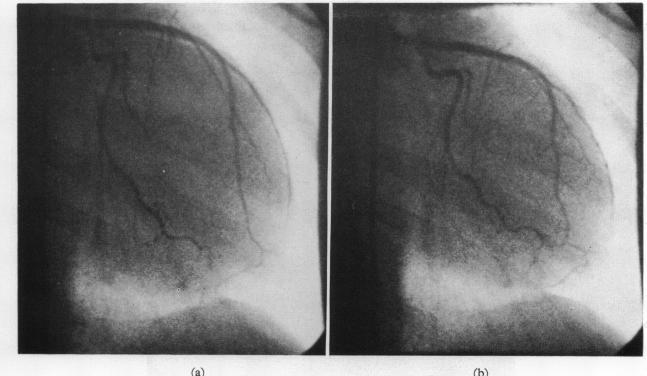

Selective coronary angiography in primary myocardial disease.

Br Heart J. 1973 Feb;35(2):165-73. doi: 10.1136/hrt.35.2.165.